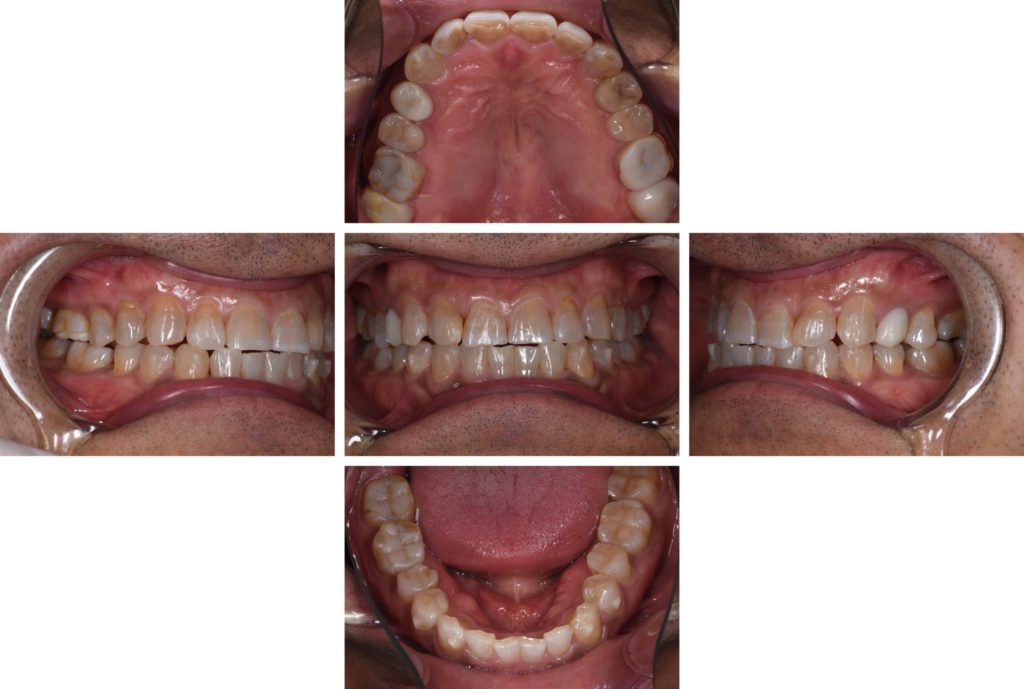

After

術前、術後比較。歯の形態、色調の改善が認められます。